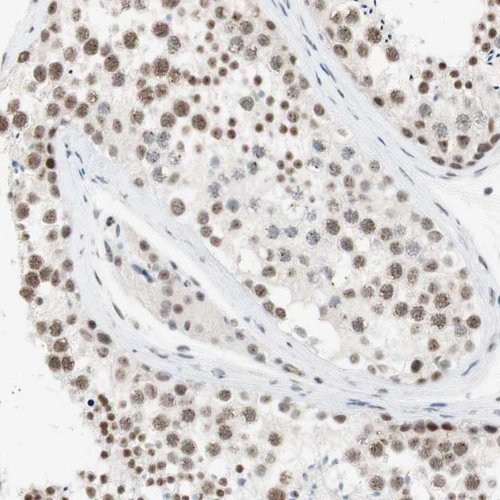

Immunohistochemical staining of human testis shows nuclear positivity in cells in seminiferous ducts and Leydig cells.